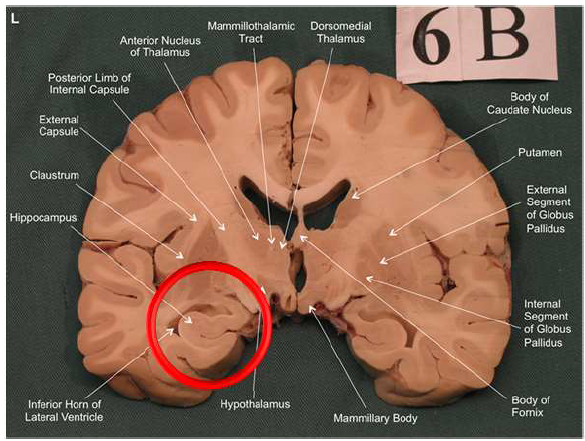

What is the fornix of the hippocampus?

Hippocampus output pathway (C-shaped)

Connects hippocampus to hypothalamus/mamillary bodies

Carries information to and from hippocampus

Important for memory consolidation and retrieval

What is this?

hippocampal fornix

Association areas activate the hippocampus, which reverberates in the Papez circuit until information is stored permanently

Hippocampus → fornix → mamillary bodies → anterior thalamic nucleus → cingulate cortex → hypothalamus